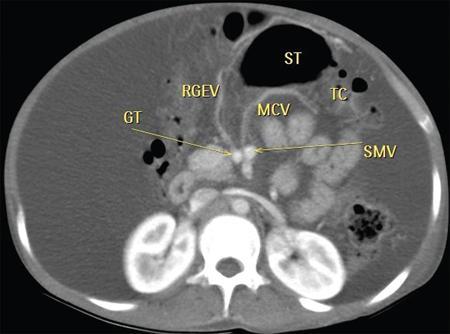

Neera Kohli, Anit Parihar Objectives: To provide the readers with a comprehensive, simplified, lucid, well-illustrated and well-presented latest account of the anatomy, functions, and childhood diseases of the mesentery. Key terms: Mesentery, anatomy, functions, infections, inflammation, neoplasia, cysts, malrotation, vasculitis, textiloma, hernias. Learning objectives: To approach a clinical condition of the mesentery in a logical and comprehensive manner so as to help the patient maximally. Increasing number of researchers, anatomists, radiologists, treating physicians and surgeons are now considering the mesentery as a separate organ. Serious attempt has been made by the authors to stick to the new theory while choosing and describing the various paediatric diseases to be included in this chapter. Likewise, each condition has been described as inclusively as possible. Mesentery develops from the splanchnic mesoderm. It has two parts: a ventral part that forms the mesentery of the abdominal part of oesophagus, the lesser omentum and mesentery of the first part and proximal half of the second part of the duodenum. The other is the dorsal part that runs below the diaphragm, from the oesophagogastric junction to the anorectal junction forming the mesentery of rest of the gastrointestinal tract (GI) including the greater omentum. It consists of fat, and has blood vessels, nerves and lymphatics running that supply the GI. Interest in the mesentery was reactivated when Heald in 1988 demonstrated that tumour recurrence following rectal cancer surgery was dramatically decreased if the mesorectum was removed. Heald’s work was the true start of mesenteric-based surgery. Hohenberger in 2009, focused on the mesocolic region, and showed that intestinal tumour recurrence was minimized, if the mesocolon was surgically excised intact. Heald and Hohenberger thus prompted a renaissance in the study of the mesentery and abdominal anatomy. Following their findings, research was done which demonstrated that the mesentery below the duodenum is continuous, and that the large and small intestine is centrally connected to the rest of the body, by the mesentery. Mesentery originates or has root posteriorly, at the level of origin of the superior mesenteric artery (SMA), as these findings clarified its shape, they marked the start of the scientific study of the mesentery and led to the proposal that it be reclassified an organ. Subsequent research showed that abdominal digestive organs, that is, liver, spleen, intestine and pancreas develop either on or in it. This relationship is retained into adulthood, so abdominal digestive organs are directly connected to the mesentery or we can say that they are ‘mesenteric’ in embryological origin and anatomical position (Fig. 7.10.1). Accordingly, all abdominal and pelvic organs belong either to a mesenteric or a non-mesenteric domain. This model explains the positional anatomy of all abdominal digestive organs and associated vasculature. Moreover, it explains the peritoneal landscape and enables differentiation of peritoneum from the mesentery. Hence, the mesentery should be subjected to the same investigatory focus that is applied to other organs and systems. One should be well versed with the normal appearances of mesentery on USG, CT and MRI (Fig. 7.10.2 A–C). Wherever mesentery is attached, a fascia (Toldt’s fascia) runs between the mesentery and the abdominal wall. This mechanism of anchorage is important. Second mechanism of anchorage involves the peritoneum which lines the abdominal wall and is reflected onto viscera as the ‘peritoneal reflection’. The mesentery, Toldt’s fascia, and peritoneal reflection are continuous. The third mechanism of anchoring is the vascular pedicle. Further mesenteries may be divided into true and specialized mesenteries. True mesenteries connect abdominal organs to the posterior wall of the abdominal cavity. These are the small bowel mesentery, the transverse mesocolon, and the sigmoid mesentery. Rest are specialized mesenteries. They do not attach organs to the posterior wall of the abdomen. The mesenteric organ is responsible for the development of systemic inflammation, such as the systemic inflammatory response syndrome (SIRS) and multiple organ dysfunction syndromes (MODS). Proinflammatory cytokines are produced in the intestine and mesentery and are then systemically distributed via mesenteric lymph. These contribute to a systemic inflammatory response, for example, post injury. The mesentery comprises a connective tissue lattice within which adipocytes are present in large numbers. Due to production of cytokines like C-reactive proteins (CRP), resistin, leptin and adiponectin by the mesentery it is considered responsible for glycemic/lipidemic disorders. Mesentery is a big source of secretion of CRP as it contains the largest part of visceral fat hence it is being implicated in diabetes and metabolic syndrome, suggesting that mesenteric adipocytes play a role in the pathobiology of these disorders. Further, visceral tissue plays an important role in immune regulation and may function as a proinflammatory agent. In mesenteric inflammation, both tissue and circulating fibrocyte levels are elevated and are associated with autoimmunity (e.g. systemic scleroderma, rheumatoid arthritis, Grave’s disease), inflammation, and fibrosis (idiopathic pulmonary fibrosis). These can differentiate into adipocytes or fibroblasts and are associated with autoimmunity in conditions such as: systemic scleroderma, rheumatoid arthritis, Grave’s disease and idiopathic pulmonary fibrosis. Fibrocytes also have the ability to act as proinflammatory cells by secreting cytokines. Although currently neutrophils, lymphocytes, adipocytes, and fibrocytes are being studied in details, it is quite possible that there are other varieties of cells involved in mesenteric inflammation. ANML, also known as primary mesenteric lymphadenitis, is a self-limiting inflammatory disease of the mesenteric lymph nodes of right lower quadrant. Clinically it closely resembles acute appendicitis (AA). It occurs in children, adolescents and young adults. CRP and leukocyte count do not help much in differentiating these two conditions. Ultrasonography is the investigation of choice for diagnosing ANML. If three or more mesenteric lymph nodes with a short-axis diameter of 8 mm or more without any associated inflammatory process is identified then ANML is a strong possibility (Fig. 7.10.5A and B). CT if needed, is usually reserved for older patients. Radiologists should try to visualize the appendix as well. If the appendix is normal then it favours diagnosis of ANML. Occasionally, very large mesenteric lymph nodes may result in vascular compromise leading to ischemic colitis. Secondary mesenteric lymphadenitis is associated with some detectable intraabdominal inflammatory process. ANML is more common than AA in the first decade of life. AA becomes more frequent in the second decade and is distinctly uncommon after the age of 20. Boys are more commonly affected. Common symptoms are: fever, vomiting, change in consistency and frequency of stools and mild pain to severe colic. The pain mimics that of AA as it is felt in the right iliac fossa as well as in the periumbilical area. Although, this condition is referred to as nonspecific yet causative micro-organisms have been identified. These are: Several viruses, Yersinia enterocolitica, Helicobacter jejuni, Campylobacter jejuni, Salmonella spp., Shigella spp. and Mycobacterium tuberculosis. Yersinia enterocolitica is considered the most common pathogen in temperate regions. It has been observed that, when ANML or appendicitis occurs in childhood or adolescence, there is a significantly reduced risk of ulcerative colitis later in life. CD is a chronic inflammatory disease that affects the GI and adjacent mesentery in the paediatric and adult populations. Its prevalence is increasing worldwide. Mesentery of patients with CD has more fat tissue. These fat cells can produce proteins such as CRP which is associated with inflammation. This may be the cause of increased inflammation and bacterial invasion. Imaging studies have very vividly shown mesenteric and intestinal involvement in CD. Following are the findings noted in CD of the mesentery: Increased vascularity, oedema, lymphadenopathy, proliferation of the fibrous and fatty tissue, and increased density of fat. Besides these, stenosis and sacculations in the mesentery are also seen. Computed tomography (CT), magnetic resonance (MR) enterography, and strain elastography findings are demonstrated equally well in the mesentery and contiguous intestine. CT enterography is a better modality for assessing mesenteric abnormalities. Sakurai et al. have demonstrated radiological evidence of mesenteric hypervascularity (‘comb sign’) and nodal enlargement correlated with endoscopic evidence of mucosal ulceration. Gale et al. compared MR and CT enterography findings in 84 children and adolescents having active CD with radiological findings in their mesentery. They concluded that mesenteric hypervascularity, oedema, fibrofatty proliferation and lymphadenopathy correlated well with active mucosal disease. Mesenteric vascular diseases like arterial emboli, venous thrombi, and venous congestion have been reported in CD. These may be complicated by bowel ischemia and perforation. Lymphoma may arise in the mesentery in CD, without involvement of other organs, so neoplasia must be considered as a differential of a mesenteric mass arising in CD. It was first reported as retractile SM in 1924. SM is a rare, benign idiopathic, chronic, fibroinflammatory disease of the small bowel mesentery. It is of three types: mesenteric lipodystrophy, mesenteric panniculitis and retractile mesenteritis. Prevalence of mesenteric panniculitis is 0.6%. All three have distinct radiographic features, however, there is considerable overlap. Mesenteric panniculitis (MP) is a localized, chronic inflammatory process, seldom advancing to become fibrosis which may be florid. SM on sonography is seen as a hyperechoic, vessel encasing mass. This mass can also cause adjacent bowel displacement. This same feature is seen as halo sign on CT but without occlusion. CT can also show significant lymphadenopathy, bowel displacement and increase in the enhancement of surrounding fat labelled as ‘misty mesentery’, which is characteristic of MP. These findings are useful in differentiating SM from lymphomas and desmoids. The soft tissue nodules and calcifications in the vicinity are encased by dense tissue and fat leading to formation of a ‘pseudocapsule’. Though ‘Halo sign’ and ‘pseudocapsule’ are dependable signs yet they do not qualify to be called pathognomonic for SM. On the other hand, MRI has a higher sensitivity than CT for detecting SM. On MRI, mesenteric panniculitis and scattered lymph nodes are hyperintense on T2WI. In contrast, retractile mesenteritis has numerous strands of soft tissue, due to fibrosis with low signal on T1WI and T2WI MRI. Tuberculosis of mesenteric lymph nodes, along with peritoneal tuberculosis is seen in 45%–80% of children with an abdominal disease. Mesenteric lymph nodes involvement is seen frequently. Lymph nodes can get involved through lymphatic drainage of infected organs, retrograde lymphatic spread from intrathoracic disease, or due to hematogenous spread (Fig. 7.10.6). Tuberculosis of intraabdominal lymph nodes may occur without involvement of the intestine and peritoneum (Fig. 7.10.7). In such cases, it is associated with enlarged extra-abdominal superficial lymph nodes. The diseased involved lymph nodes may regress over time with or without calcification, can form inflammatory masses with possibility of abscess formation later on. Fistulae and ascites may also be seen. Ultrasound is the investigation of choice. Generally, lymph nodes show a central hypoechoic area due to central liquefaction; they can form conglomerates and infiltrate the omental fat, forming omental cake. Ultrasound also detects ascites very well. Ascitic fluid may be clear or contain fibrin strands, loculations and debris. The differential diagnosis of ascitic septations includes lymphoma, other carcinomas, and pyogenic peritonitis. Echogenicity of mesentery is increased in mesenteric tuberculosis. CT has a greater sensitivity than ultrasound in detecting mesenteric lymphadenopathy. Presence of lymph nodes with calcifications or with the typical low-density centres due to liquefaction and a peripheral ring enhancement favours tuberculosis. Solid organs like liver and spleen can have calcification. CT can easily detect inflammatory masses consisting of lymph nodes, omentum and bowel (called omental cakes). In children, MRI has the usual advantage of the fact that there is no ionizing radiation. However, sedation may be required due to a long study time. MRI findings of TB lymphadenitis display a predominant peripheral rim enhancement with or without a multilocular appearance, with a central non-enhancing lesion corresponding to caseation or liquefactive necrosis. Ascitic fluid is seen very well as a T2WI hyperintensity. Radiograph of the chest is a supportive investigation as 23% patients of proven pulmonary tuberculosis also have abdominal disease.